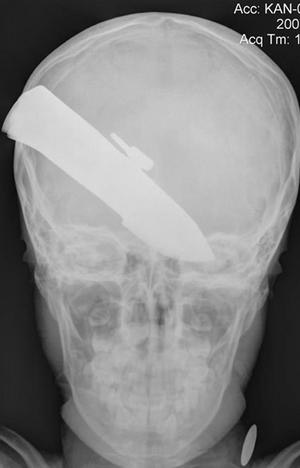

Военные хирурги из полевого госпиталя в провинции Гельманд сделали рентгеновский снимок головы мальчугана и выяснили, что в черепе мальчугана застряло 7,5 см закаленной стали. Врачи были в ужасе.

- Лезвие проткнуло черепную коробку в затылочной части. Оно аккуратно прошло между двумя полушариями мозга, не повредив ни одно из них. Поэтому любая попытка вытащить нож из головы ребенка могла просто погубить его, - рассказали военные врачи.

Хирурги провели уникальную операцию и удалили лезвие. По словам отца пострадавшего, все произошло 14 июля 2007 года.